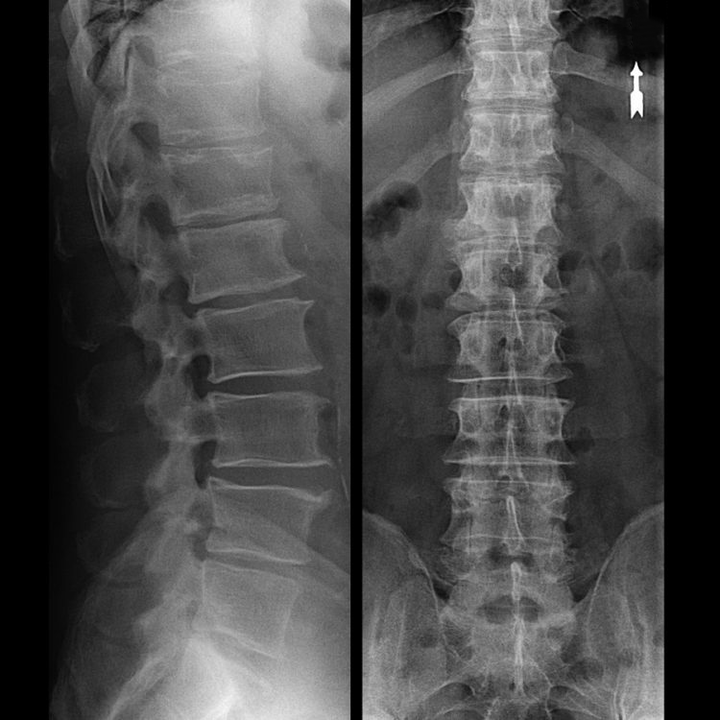

In typical cases, osteochondrosis of the cervical and cervicothoracic spine occurs as described above.Therefore, the main stage of diagnosis has been and remains the identification of the patient's complaints, establishing the presence of concomitant muscle spasms by simple palpation of the muscles along the spine.Is it possible to confirm the diagnosis of osteochondrosis by radiological examination?

An "X-ray" of the cervical spine, and even with functional tests of flexion and extension, does not show cartilage, since its tissue transmitsFragile and dehydrated intervertebral discs.Functional tests can confirm the diagnosis of cervical spine instability.

Since the discs themselves can only be seen using CT or MRI, magnetic resonance and X-ray CT are indicated to clarify the internal structure of cartilage and formations such as protrusions and hernias.Thus, with the help of these methods, a diagnosis is made accurately and the tomography result is an indication, or even a topical guide, for surgical treatment of a hernia in the neurosurgery department.

- You can regularly do at least one x-ray of the lumbar spine in two projections, or an MRI, to find out if the hernia, if any, is progressing;